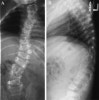

X-ray : 선천성 척추 측만증(Congenital scoliosis)

Lateral view에서 후만변형이 동반되었는지를 관찰합니다.

뒤쪽의 반척추증 : 잦은 후만변형을 유발합니다.